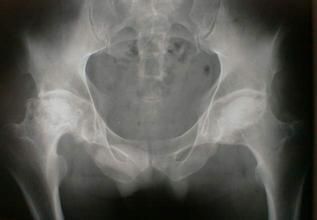

导读: 股骨头坏死是中老年人比较常见的骨关节病之一,可引起股骨头疼痛,从间断性疼痛会逐渐发展为持续性疼痛,然后在引起肌肉痉挛、关节活动受限等。如果不进行缓解呵护,甚至可能致残。